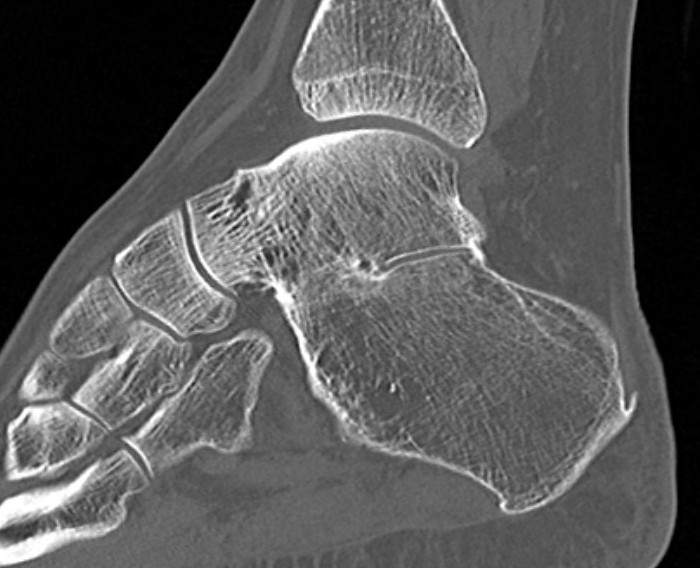

CT

Open Calcaneo-navicular bar resection